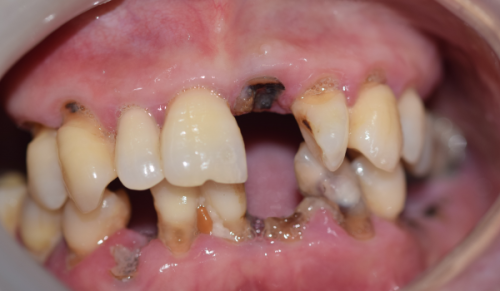

最近,网上有一些关于北京整齐娃娃口腔医院“太坑人”的言论,其实这纯属谣传。医院拥有超多实例好评,特别多患者在接受治疗后都对医院的技术和服务赞不绝口。在种植和矫正技术方面,医院更是在行。医院引进了国内外精良的种植和矫正技术,能够为患者提供更加精细、效率高的治疗。例如,在种植牙方面,采用了精良的种植系统,能够大大缩短种植时间,提高种植成功几率。在牙齿矫正方面,有多种矫正方案可供选择,如传统金属矫正、隐形矫正等,满足了不同患者的需求。